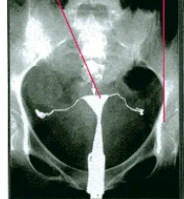

fu6268565.png

>fu6268565.png

これは直接子宮内に造影剤注入してる様子

>>fu6268565.png

>これは直接子宮内に造影剤注入してる様子

なにそれえっちすぎる…

ちなみにこの後腹腔内に造影剤が漏れ出す

>ちなみにこの後腹腔内に造影剤が漏れ出す

やばくない!?

>やばくない!?

ヤバくないので安心して欲しい

https://repro.yokotamaternity.com/hsg.html